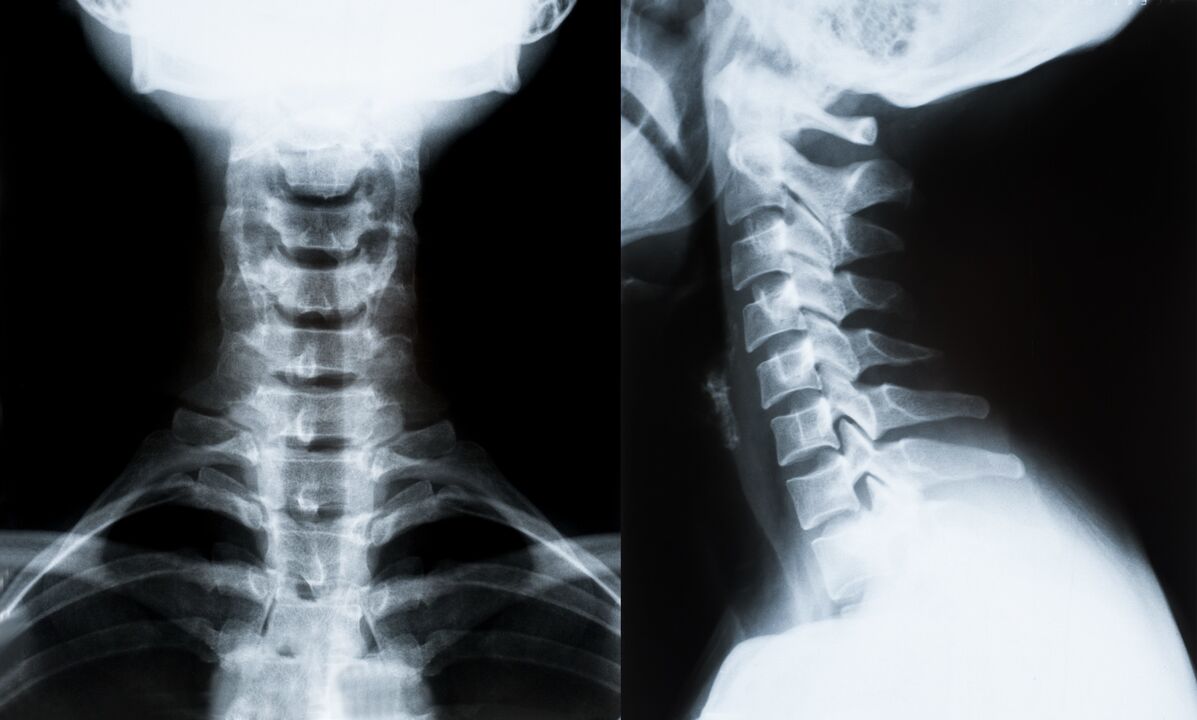

A nyaki gerinc osteochondrosisának diagnosztizálásának és kezelésének további meghatározásának fő módszerei:

- röntgen. A legkevésbé hatékony, de hagyományos diagnosztikai módszer.

- A mágneses rezonancia képalkotás a leghatékonyabb diagnosztikai módszer. A páciens ilyen típusú vizsgálatával minden szükséges struktúra látható.

- Ha a változásokat mérni kell, számítógépes tomográfiát alkalmaznak. Meghatározza a sérvek és egyéb dolgok jelenlétét.

- Az utolsó módszer az ultrahangos duplex szkennelés. Ez a kutatási módszer meghatározza a véráramlás sebességét az artériákban.

Lehetetlen pontosan meghatározni a gerincbetegséget otthon.